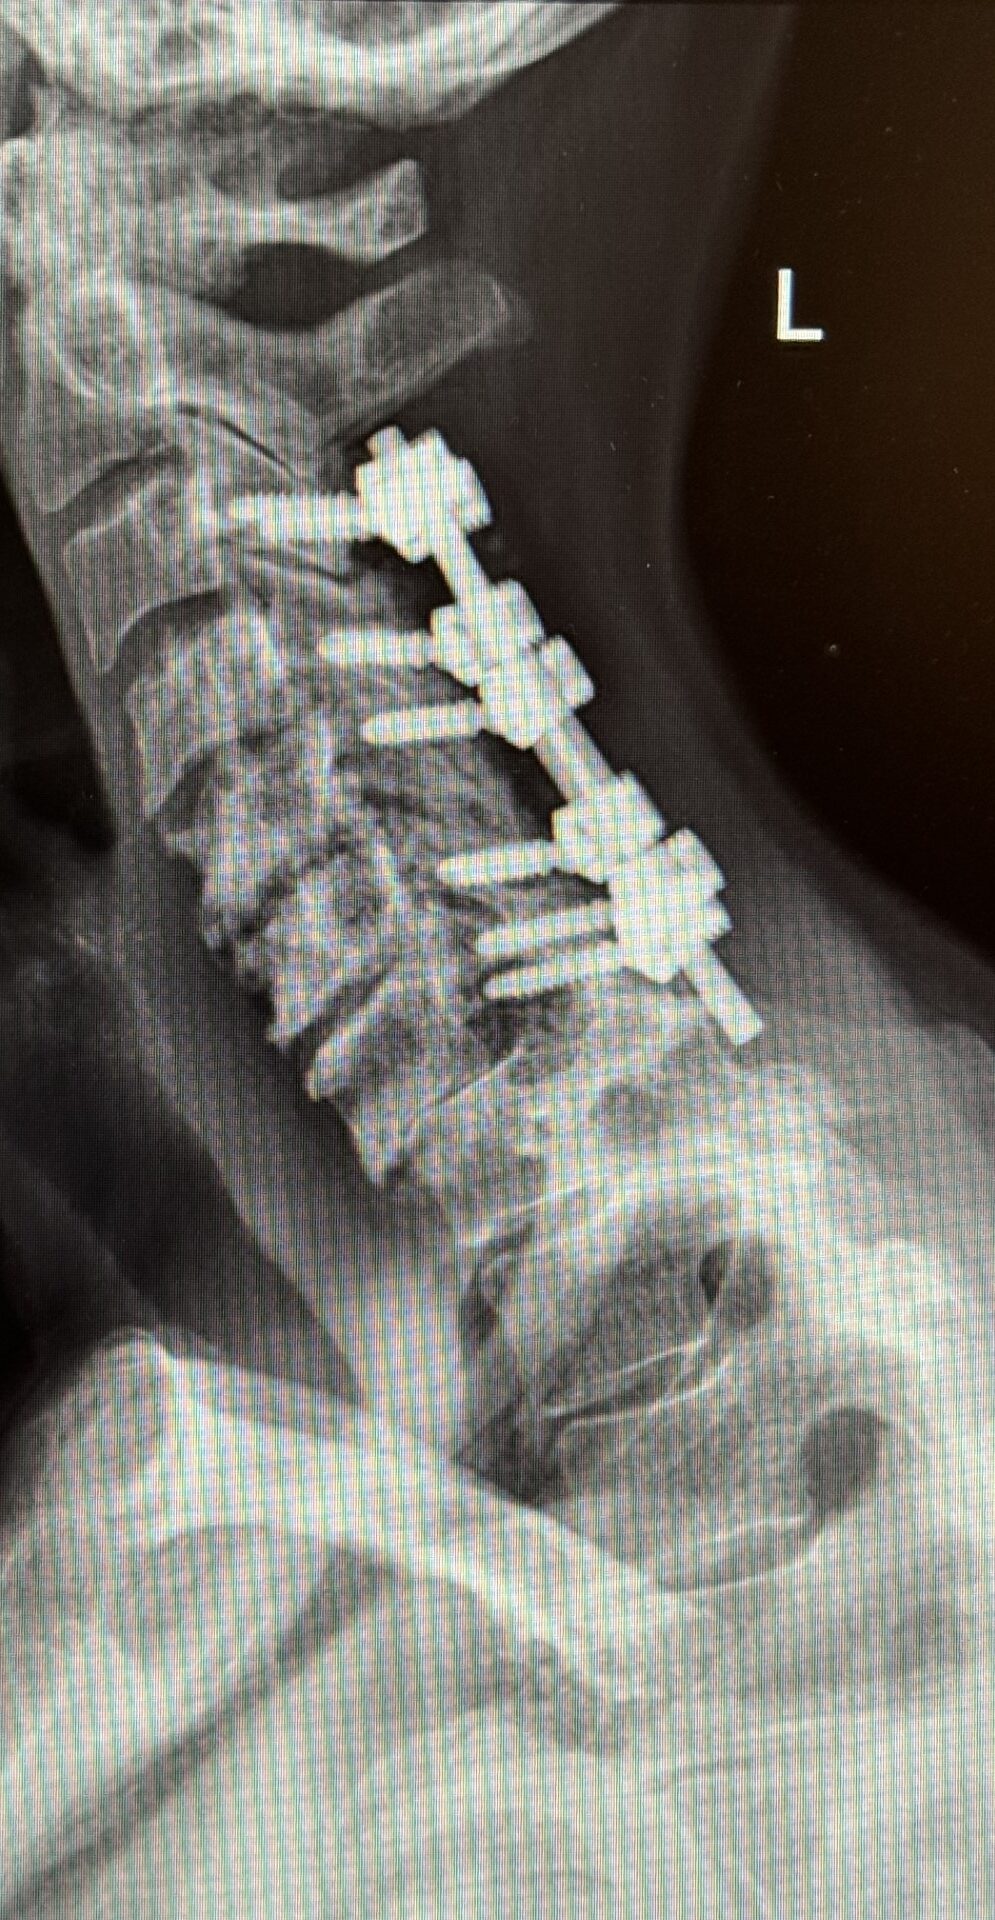

The patient underwent a one-day, two-stage procedure. Stage 1 was a C6-7, C7-T1 anterior cervical discectomy and fusion with reduction of the anterolisthesis and correction of the kyphosis.

Stage 1 was immediately followed by Stage 2 which was extension of her posterior instrumentation and fusion from C3 down to T3. Neuro-navigation was used to assist with the difficult anatomy of the upper thoracic spine.

The patient had an uneventful postoperative course with significant improvement in her preoperative symptoms and is now able to maintain a good posture (Fig 2 right).